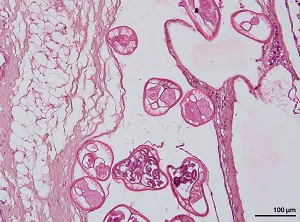

Brugia spp. have typical features of filarial nematodes in cross-section. Females reach a maximum diameter of 180 µm; males are smaller (up to 90 µm). The intestine is small and females have two uterine tubes containing developing microfilariae. The musculature is comprised of few coelomyarian cells per quadrant and the cuticle is smooth.